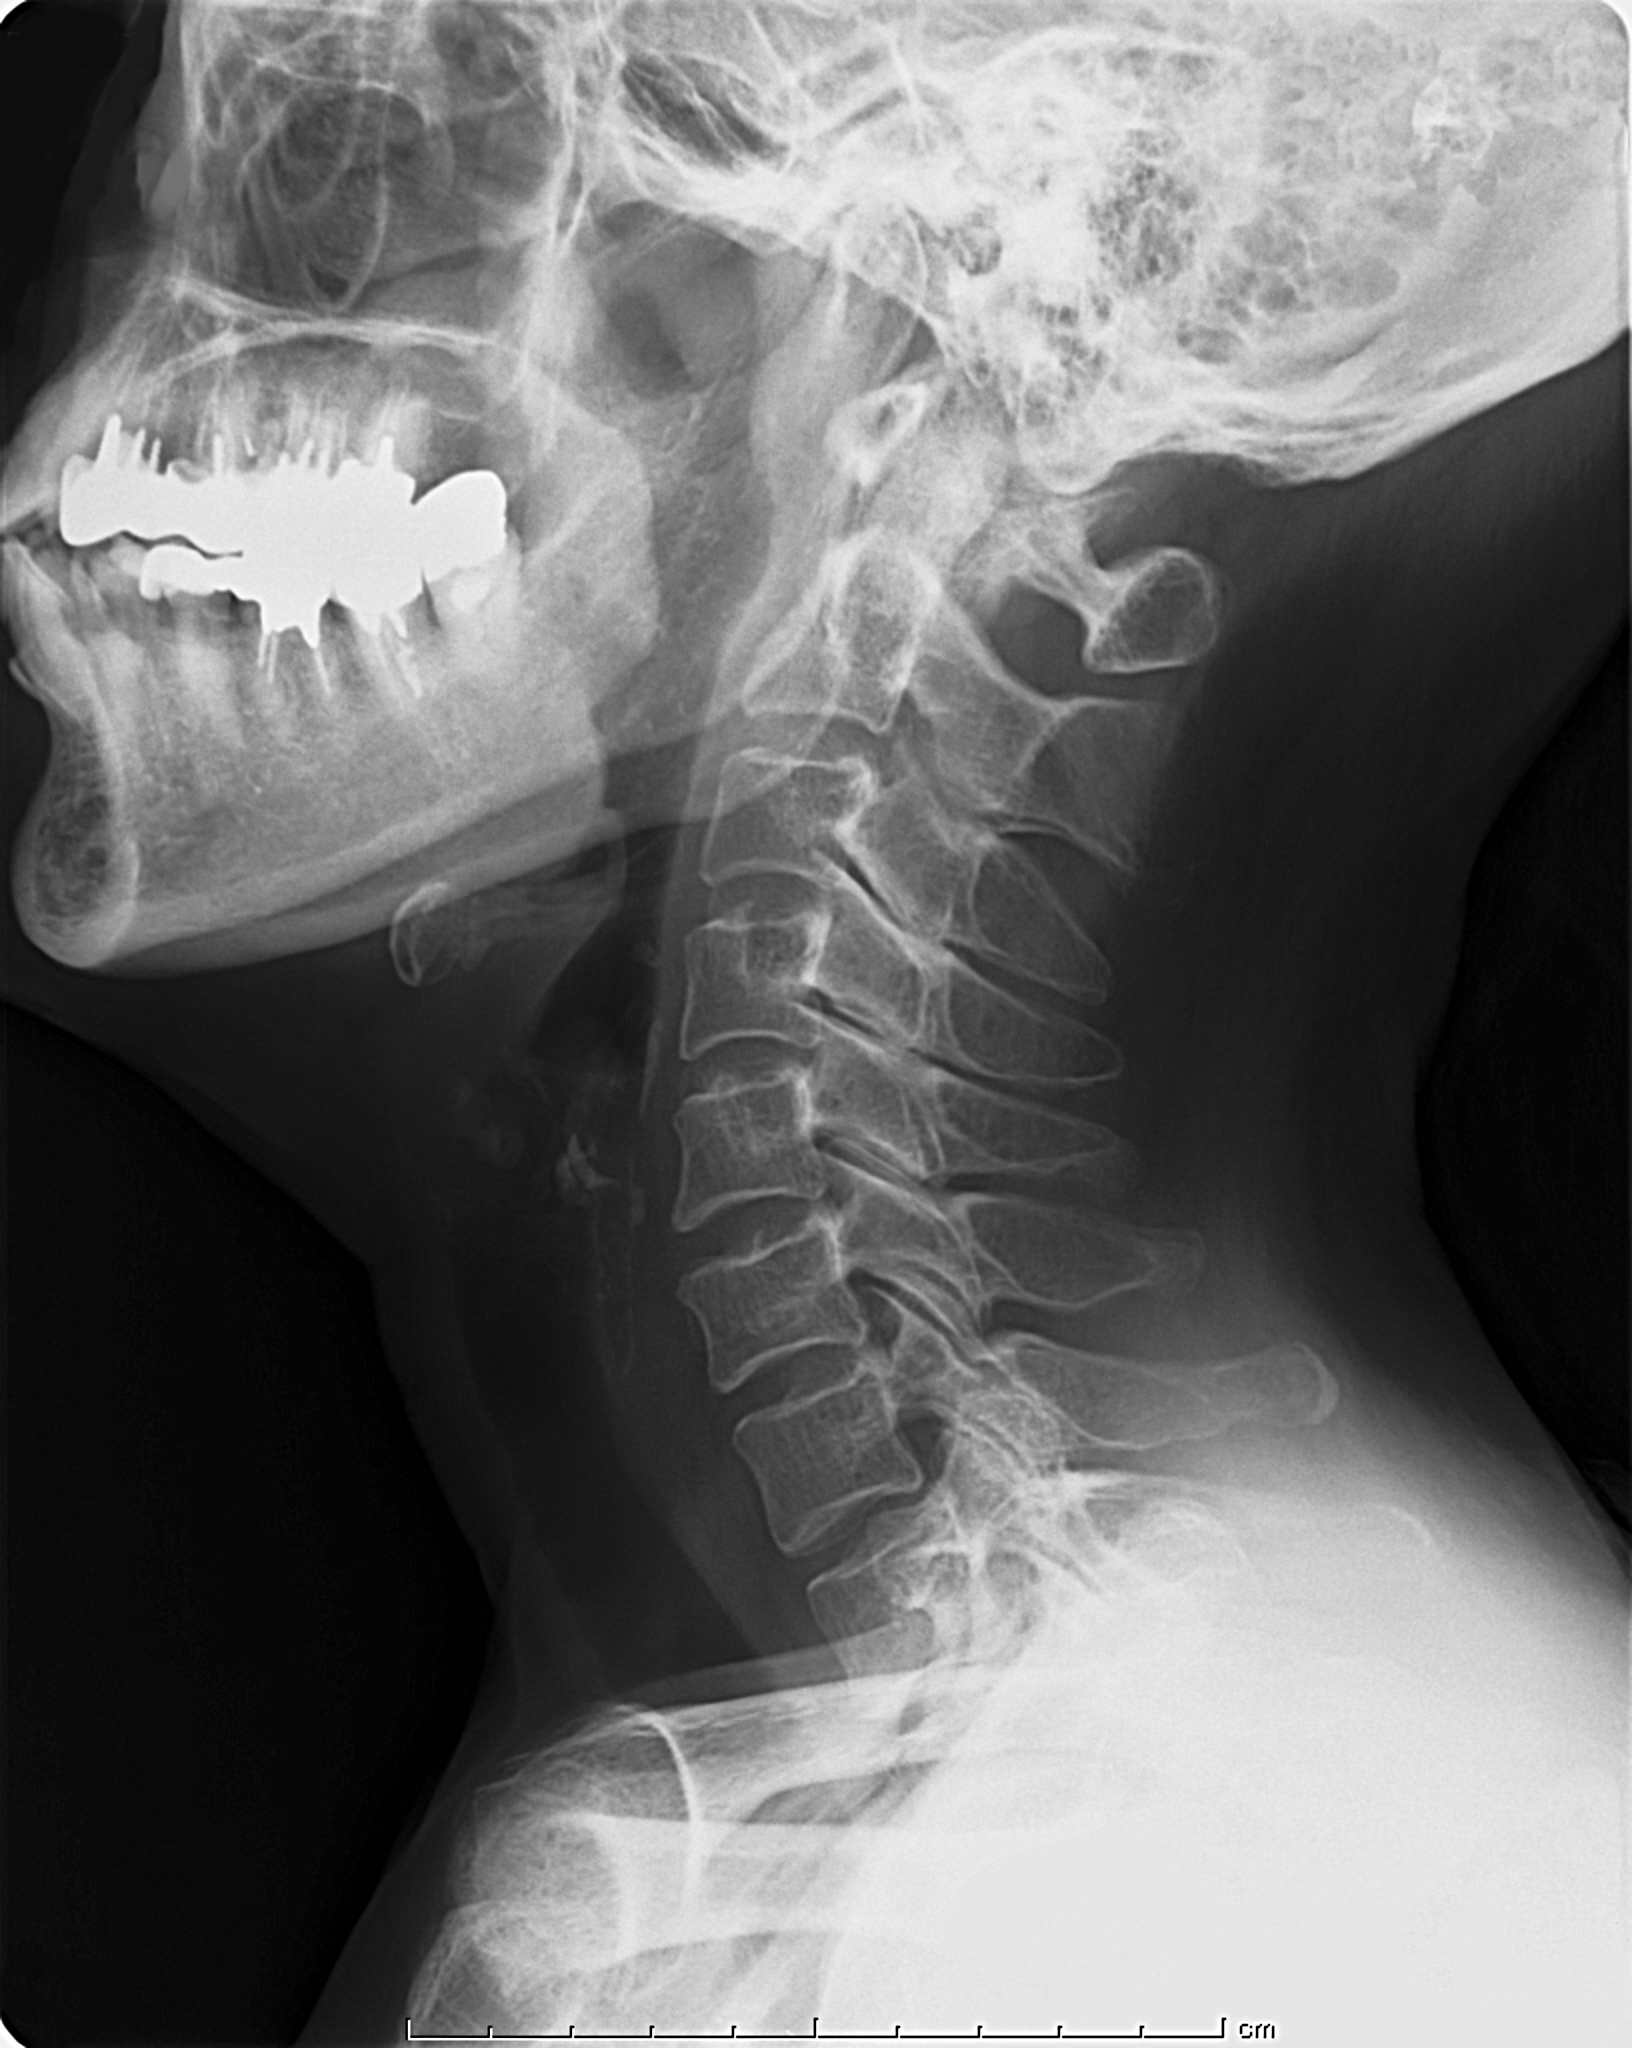

file2_title

正常な首(頚X線)